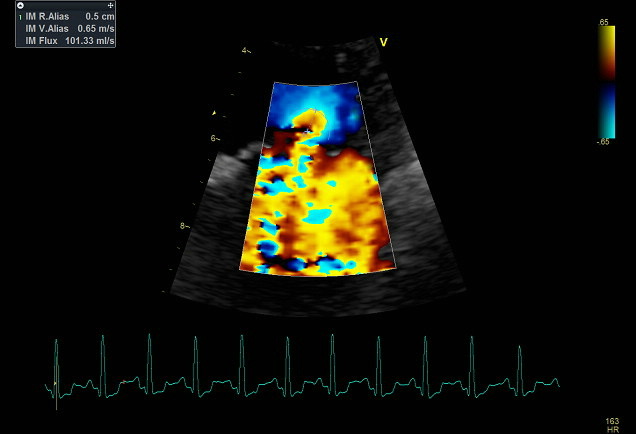

CONSULTATION DE CARDIOLOGIE, ECHOGRAPHIE DOPPLER

L’échographie est un examen indolore qui permet de visualiser la morphologie cardiaque et d’évaluer les flux sanguins au sein du cœur, on peut alors estimer la fonction cardiaque, cet examen se déroule couché ou debout, sans tranquilisation dans la majorité des cas.